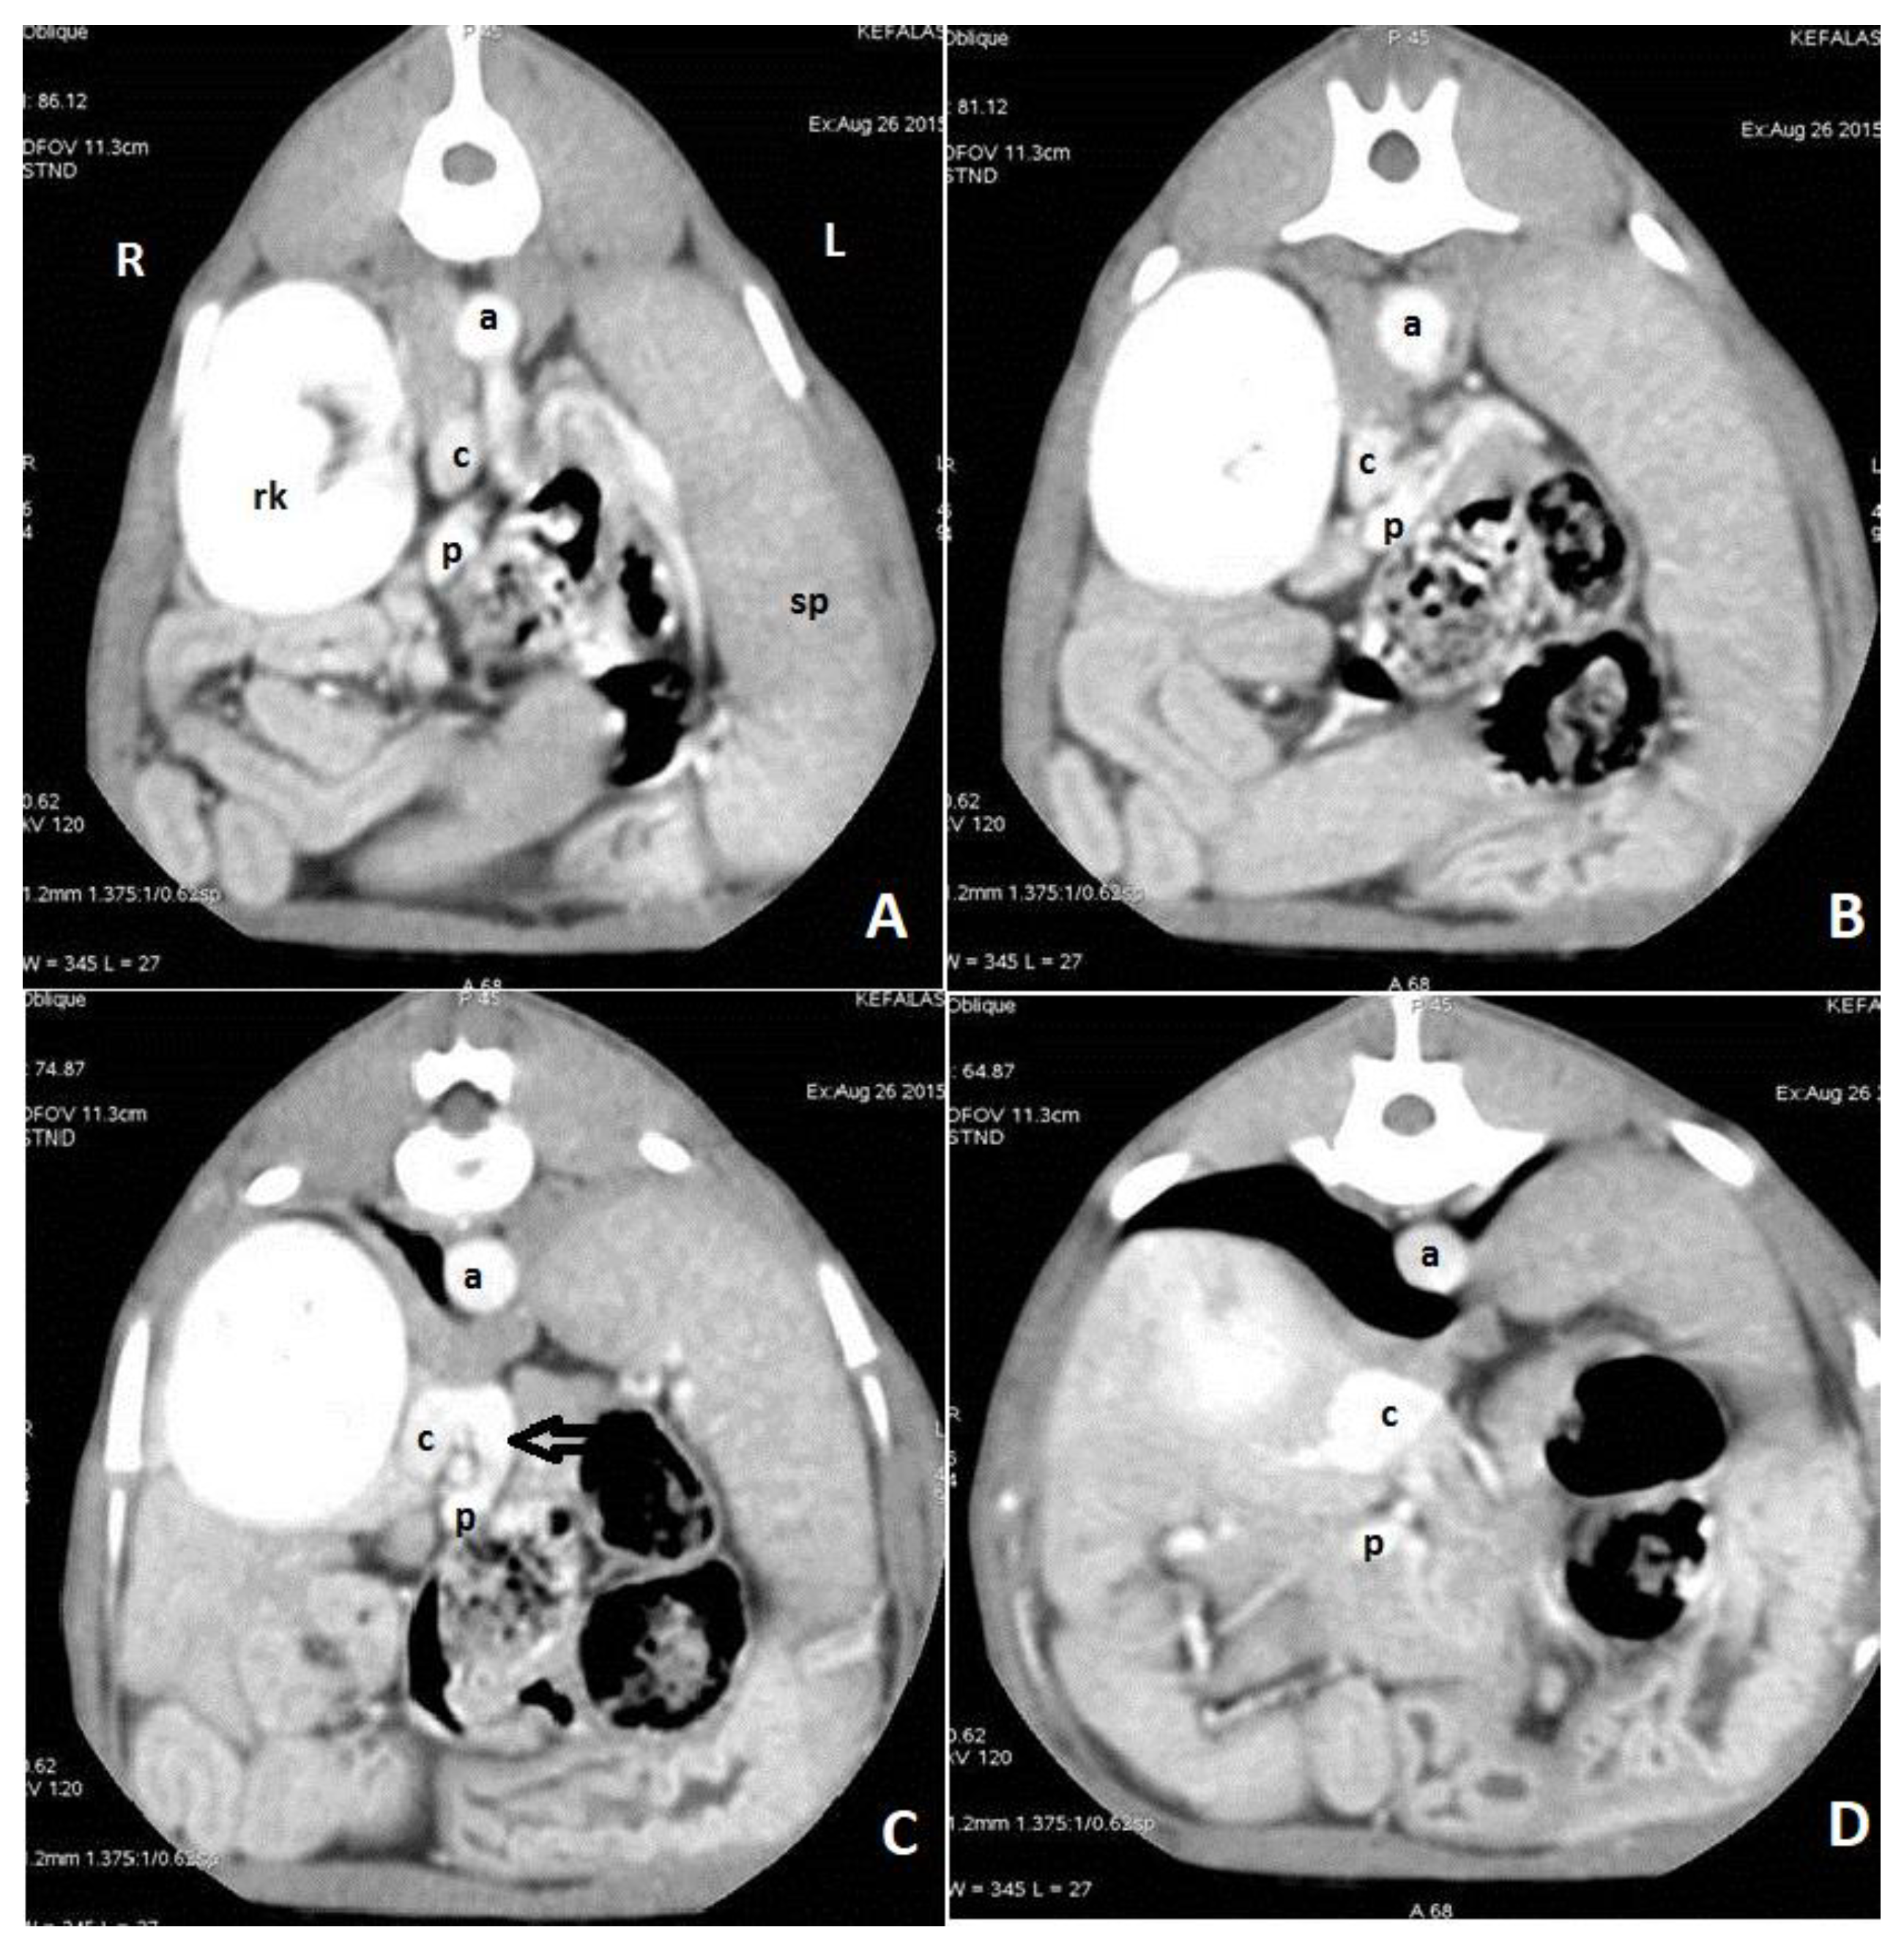

6. Clinical Signs/Physical Examination

9. Diagnostic Imaging